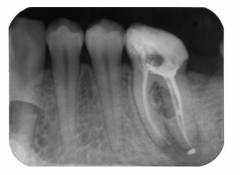

| Рентгенография | Применяется для выяснения особенностей строения зуба и степени заболевания. |

Каждая форма пульпита требует специфического подхода к лечению. Перед стоматологическими процедурами обязательно проводится местная анестезия и удаление пораженных тканей. Рентгеновский снимок — завершающий этап лечения для контроля его эффективности.

Что может сделать врач, чтобы предотвратить повторный пульпит? Опытные стоматологи рекомендуют тщательно пломбировать все каналы и делать контрольный снимок, чтобы убедиться, что каналы равномерно и плотно заполнены материалом, без пустот, где могут размножаться бактерии.

| Рентгенография | Широко используется для изучения строения зуба, степени заболевания и результатов предыдущего лечения. Для коренных зубов нижней челюсти проводят внеротовое рентгенографическое обследование, а для остальных зубов — внутриротовой способ. |

Каждая форма пульпита требует индивидуального подхода к лечению. Перед стоматологическими процедурами с острым или хроническим пульпитом проводится местная анестезия и удаление пораженных кариесом тканей. Завершающим этапом является рентгенография для оценки эффективности терапии.

Что может сделать стоматолог, чтобы предотвратить повторное развитие пульпита? Опытные специалисты рекомендуют пломбировать все каналы и делать контрольный рентгеновский снимок. На снимке каналы должны быть равномерно и плотно заполнены, чтобы избежать пустот, где могут размножаться бактерии.